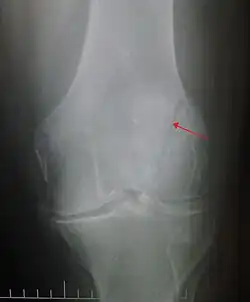

A vertical patella fracture with the fracture line marked by a black arrow

Diagnosis is based on symptoms and confirmed with X-rays.[3] In children an MRI may be required.[3]